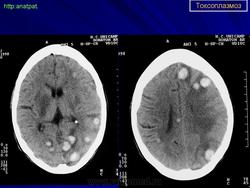

Церебральный токсоплазмоз.

Церебральный токсоплазмоз

Пато морфологи я. Патоморфологические изменения при приобретенном токсоплазмозе изучены в экспериментах на животных. Установлено, что в центральной нервной системе развиваются явления некротического перивентрикулита, мелкие очаги некроза в субкортикальном белом веществе. В сосудах головного мозга, мягкой мозговой оболочки и хориоидальных сплетениях отмечаются признаки серозно-пролиферативного воспаления. Обнаруживаются также глазные патологоанатомические изменения (типа ретинита, хориоидита, иридоциклита) и изменения во внутренних органах (сердце, легкие, печень, селезенка).

Врожденный токсоплазмоз чаще, чем приобретенный, приводит к летальному исходу. В головном мозге умерших обнаруживаются более или менее значительные очаги обызвествления, участки размягчения мозгового вещества, полости, заполненные жидкостью. Как правило, отмечается гидроцефалия, обусловленная воспалительной и рубцовой облитерацией водопровода среднего мозга, отверстий Люшка или других участков ликворных путей. Истон-чение вещества полушарий мозга может достигать степени их полного исчезновения.

Особенно характерна триада симптомов: хореоретинит, гидроцефалия, очаги обызвествления в головном мозге. Кроме того, отмечаются менингеальные знаки, тонические и клонические судороги, парезы, параличи, олигофрения.

Дифференциальная диагностика изображения